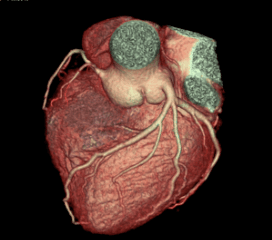

Coronary Angiogram

A CT Coronary Angiogram is a non-invasive imaging test that uses a CT scanner, and contrast dye to create detailed 3D pictures of your heart's arteries, revealing plaque, blockages, or narrowing (stenosis) that can cause heart problems like chest pain.

3D Vessel Analysis